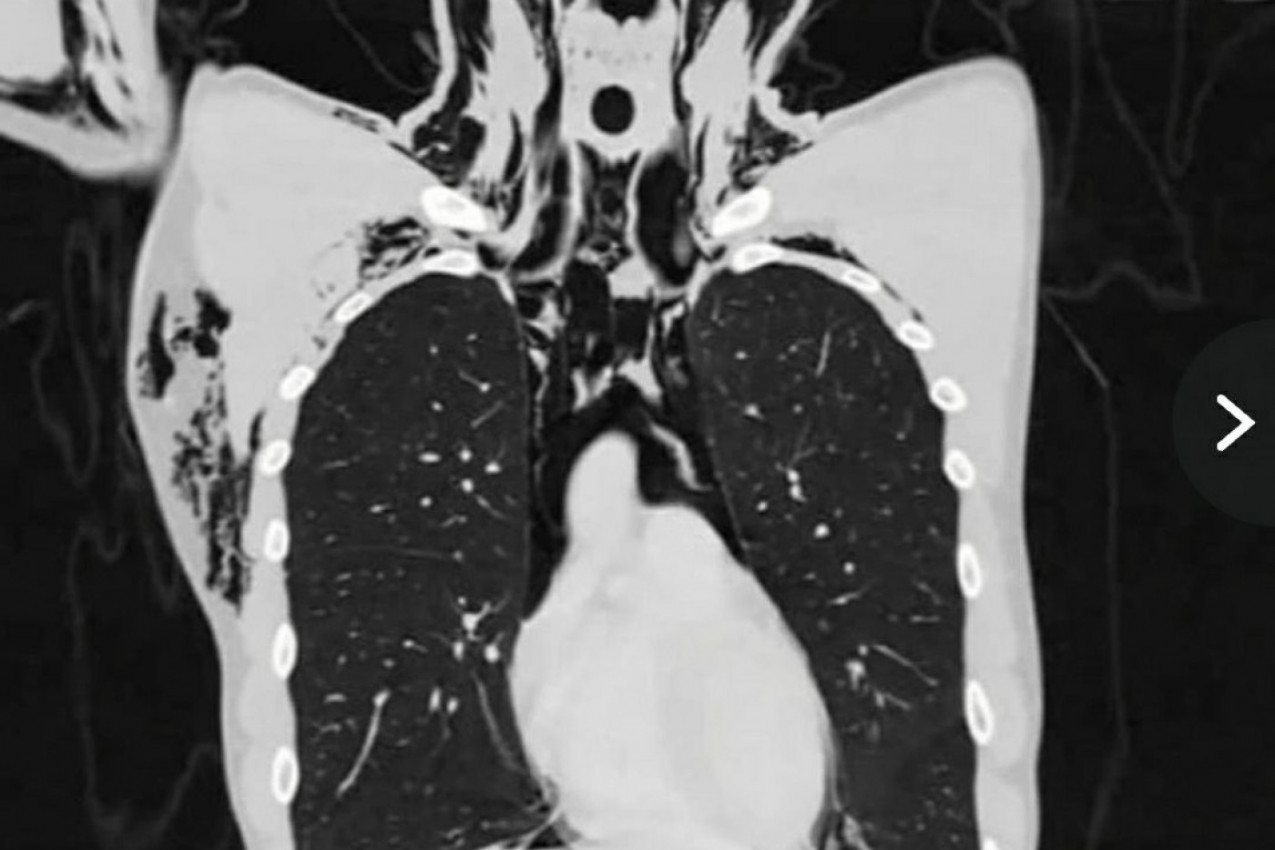

- Pacijentu je dijagnostifikovan spontani pneumomedijastijum (SPM), stanje tokom kog dolazi do "curenja" vazduha iz pluća i njegovog zadržavanja u grudnom košu - prenose mediji i napominju kako je rendgenski snimak upravo prikazao pokazivao zarobljeni vazduh između plućne maramice i grudnog koša.

Prema rečima lekara, ova izuzetno retka komplikacija s plućima najčešće se dešava muškarcima prosečne starosti do 23 godine. Švajcarac je hospitalizovan i dat mu je paracetamol u kombinaciji s drugim lekovima kako bi bolovi i otežano disanje nestali. Interesantno je da je vazduh, koji je mladiću izašao iz pluća, nekako završio i u njegovoj lobanji, što je, takođe, zabeleženo na rendgenu. U ovakvim slučajevima hirurško lečenje je retko.